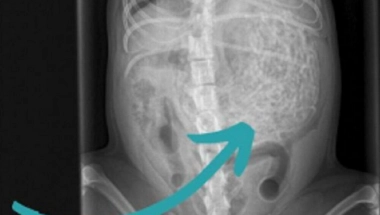

Britanska porodica doživela je pravi šok kada su psa odveli kod veterinara zbog "lošeg osećaja" koji su imali, jer je odjednom postao tih. Tamo je na ultrazvuku otkriveno da je pas pojeo 200 grama gumica za kosu!

Pregled u veterinarskoj ordinaciji pokazao je da pas ima nešto neobično u stomaku, pa su se odmah odlučili na operaciju. Izvađeno mu je oko 60 gumica teških 200 grama, a pas Hem je težak samo šest kilograma.